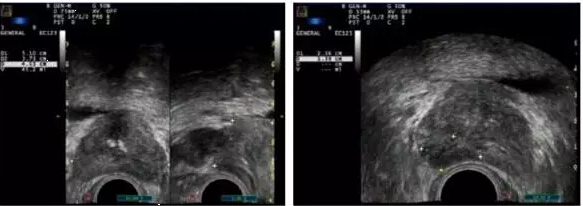

影像学检查:腹部B超(-),未发现占位。经直肠前列腺B超示:前列腺4.2 cm×4.4 cm×4.4 cm(左右×前后×上下径),体积41 ml(正常值小于20 ml);前列腺增大,向膀胱内凸出,回声欠均匀;外周区可见一低回声区,体积约3.2 cm×0.9 cm×2.2 cm,回声低,不均匀(图1)。

图1. B超表现